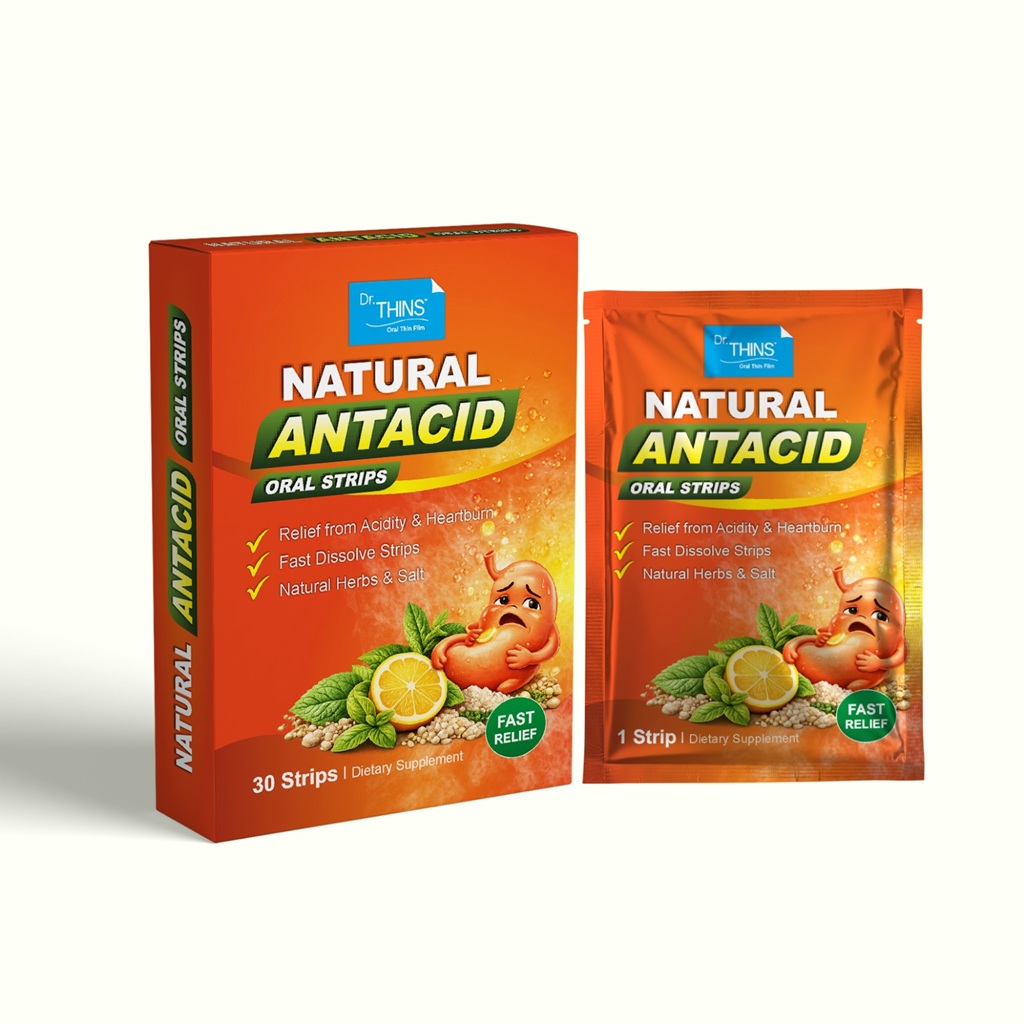

Gastrointestinal

Wellness Products

Wellness Products